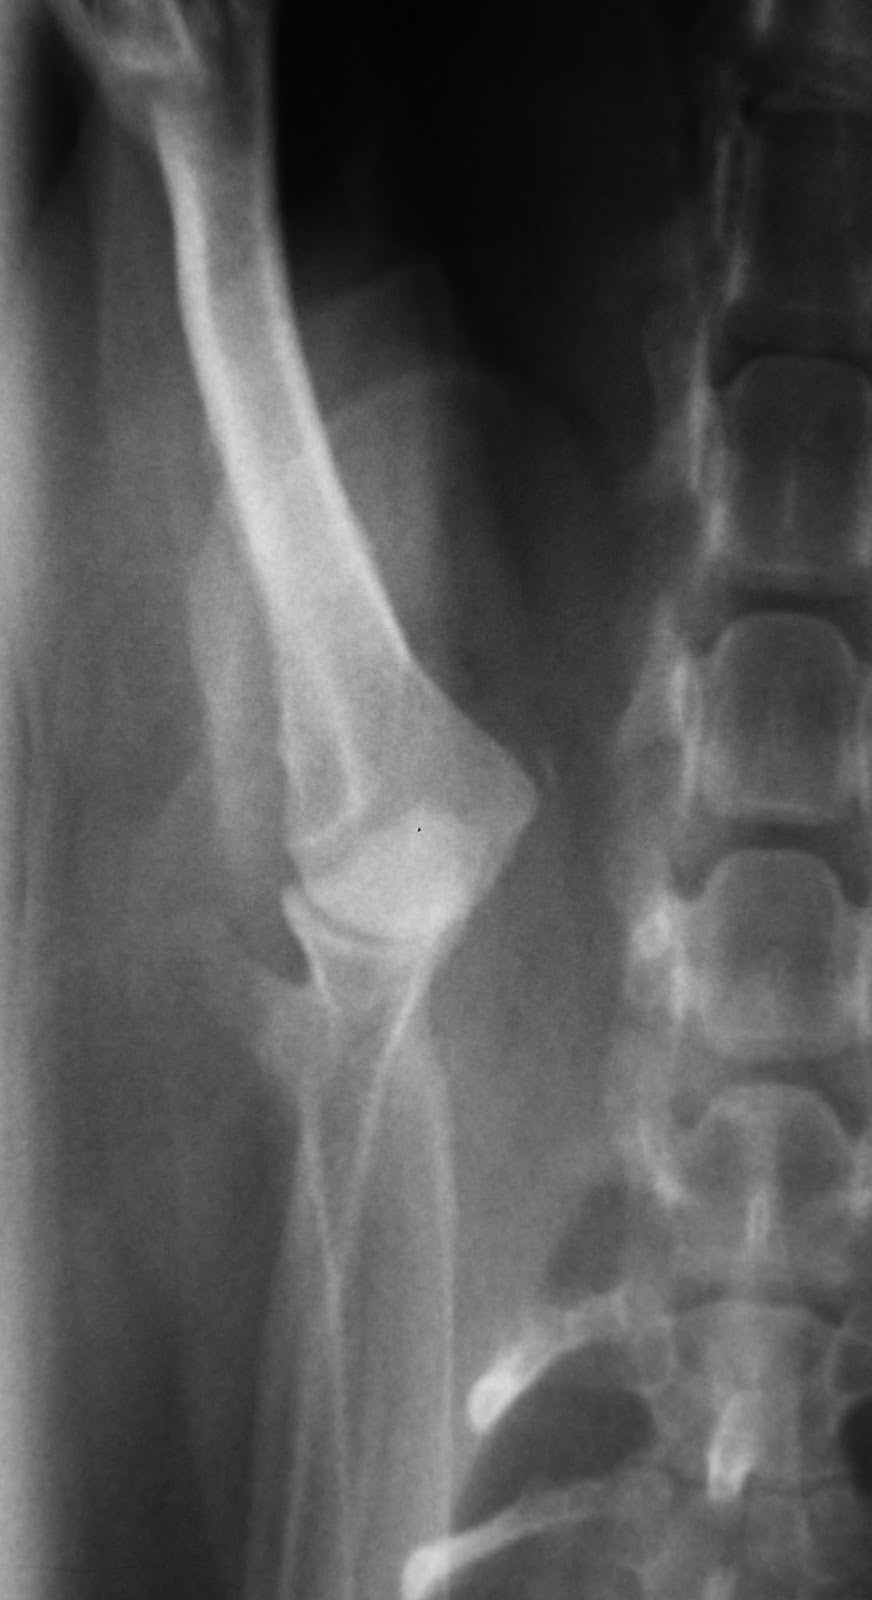

Συντηρητική ανάταξη εξαρθρήματος ώμου από Πέτρος Μπεάκος11/09/201307/12/2017Σχολιάστε Εξάρθρημα ώμου σε νανόσωμο Κανίς (Poodle toy) Μετά την ανάταξη Τοποθέτηση νάρθηκα Κοινοποιήστε: Στείλε ένα σύνδεσμο σε έναν φίλο(Ανοίγει σε νέο παράθυρο) Email Εκτύπωση(Ανοίγει σε νέο παράθυρο) Εκτύπωση Mοιραστείτε στο Facebook(Ανοίγει σε νέο παράθυρο) Facebook Μοιραστείτε στο X(Ανοίγει σε νέο παράθυρο) Χ Μου αρέσει! Φόρτωση... Σχετικά